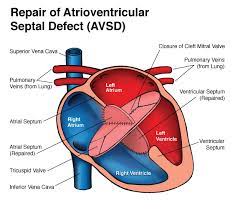

Overview

Package includes:

Days in hospital : 10 to 11 Days (For patient and one attendant)

Days in hotel : 14 Days (For patient and one attendant)

Room type in hospital : Shared

Room type in hotel : Private

Hotel category: Standard

Value added benefits of the AVSD Closure: